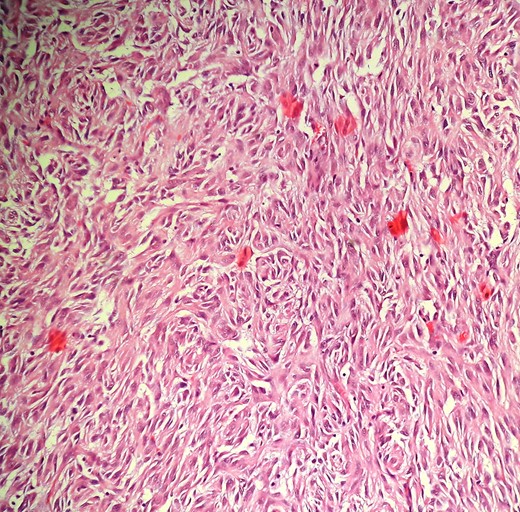

Intraoperatively, to our surprise, a tumor was arising from the mesentery of the second loop of jejunum. The entire mass was present in the right upper quadrant. It was six in number, multicentric, solid, bosselated and adhered to the serosal aspect of the jejunum. Furthermore, the omentum was wrapped around the tumor, which was in fact due to the necrotic changes in one of the tumor, with impending perforation. The tumor was excised enbloc with the jejunum with macroscopically clear margin and primarily anastomosed. Cut section showed whitish-solid tumor with whorled appearances, with one tumor with necrotic changes showing tumor enteric fistula (Fig. 2). Postoperative period was straightforward and was discharged on Day 5. Pathological examination of the specimen revealed gastrointestinal stromal tumor (GIST) of the jejunal mesentery (mitotic figure—13/50 HPF, areas of necrosis suggesting high grade), which on immunohistochemistry stained strongly for CD117 and CD34 (Fig. 3). One of the dissected lymph node in the mesentery showed tumor deposits. The patient had been on imatinib 400 mg once daily for the last 6 months, and unfortunately had liver recurrence on follow-up CT scanning.

Intraoperative (A) and cut-section (B) view of solid, lobulated (arrow) and necrotic changes in the E-GIST arising from the jejunal mesentery.